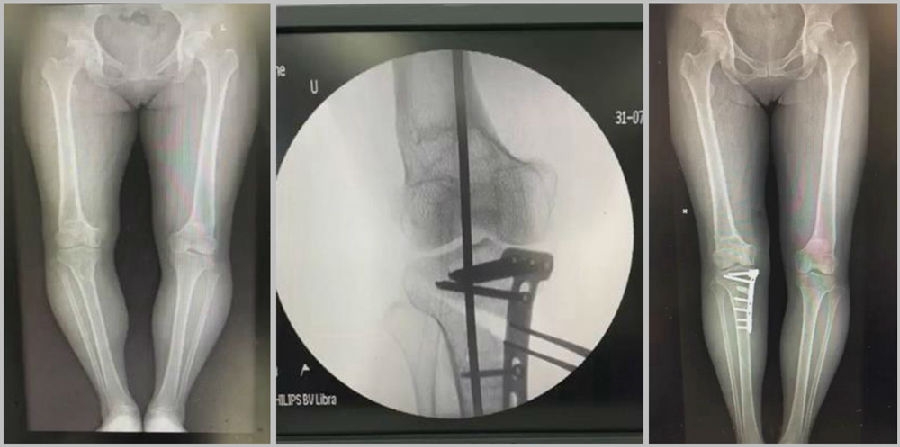

1、综合判断力线的方法

现在对于力线的判断大致通过以下几方面:①大体形态;②透视确定力线,连接股骨头中心、踝关节中心,看力线杆和膝关节中心的位置关系;③MPTA(胫骨平台关节线和胫骨侧机械轴夹角);④PSI。

1、原因及预防

(1)肢体外旋

一般来说在麻醉状态下肢体会处于外旋位,此时去测定力线的话往往需要将肢体放在旋转中立位,但是在内旋肢体的过程中会出现内翻应力,那么这种情况下判断力线会带来误差,所以通常建议大家要把手术床做一点旋转,让患肢处于自然的旋转中立位,这样再去判断力线就比较准确。

(2)MCL浅层未彻底松解

对于MCL,大多数忽视的是后侧束,如果不能把后侧束彻底松解,那么在撑开过程中往往会感觉撑不开,此时如果过度去撑开的话,会导致在关节内侧出现很大的压力,所以这时对力线会产生一定的误导。

(3)力线验证未模仿负重应力

现在所谓的目标力线应该是模仿负重时的力线。做截骨时,通常会将力线轻度外移,如果没有考虑关节内畸形、韧带松弛或是软骨磨损,那么在负重时,在内侧副韧带撑开过程中,会出现力线偏移。所以要注意,手术中间在调整目标力线时,要以应力状态下为标准。

(4)拉力螺钉加压过度

拉力螺钉的过度使用可能会引起矫形位置的角度丢失。当拉力过度时,会将力线由内侧向外侧轻度拉回,使力线丢失一部分,所以切忌过度使用。